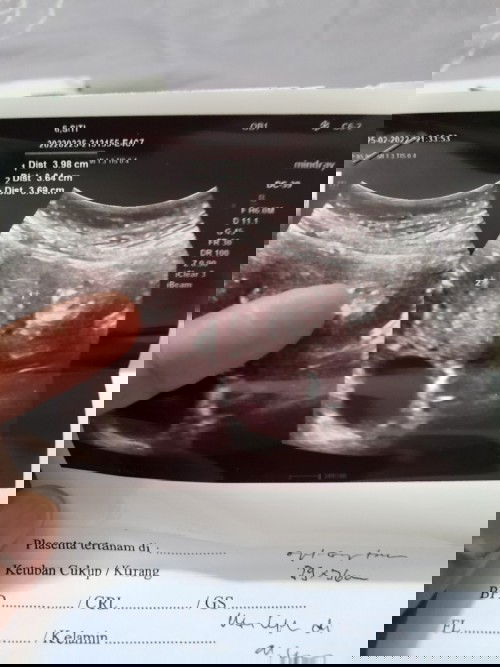

Hai Bunda... Saya ingin meminta opsi lain kepada Bunda semua.. Jadi, kemarin saya tes kehamilan dan hasilnya garis 2 setelah itu malamnya saya melakukan USG (ada fotonya), sang dokter mencurigai jika saya hamil anggur. Di sekitarnya juga terdapat banyak kantung yang dia bilang "mola" Sang dokter meminta saya kembali lagi dalam 2 minggu. Mohon opsi lain/solusinya dari Bunda, apakah saya harus kembali lagi ke dokter itu atau saya ganti dokter lain untuk meminta kepastian agar segera di tindak karna takut molanya menyebar dan ganas, Bunda. #bantusharing #hamilanggur